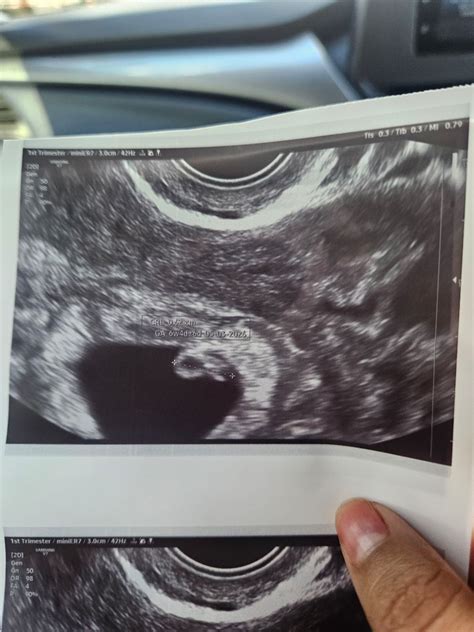

The Crown Rump Length is typically measured during an early ultrasound, often performed between 7 and 13 weeks of gestation. The procedure is usually carried out via a transvaginal ultrasound in the very early stages for better clarity, or an abdominal ultrasound as the pregnancy progresses slightly.

During the scan, the sonographer identifies the top of the baby’s head and the bottom of the rump. They then use electronic calipers on the ultrasound machine to mark these two points. The software calculates the distance between them, and the computer instantly cross-references this value with gestational age databases to provide a measurement in millimeters (mm).

While the Crown Rump Length is considered the "gold standard" for pregnancy dating, its accuracy can be influenced by a few variables. Sonographer experience is paramount; if the calipers are placed incorrectly by even a millimeter, it can change the estimated gestational age by several days. Additionally, the position of the fetus matters—if the baby is hunched over or extended, the measurement might be slightly off. This is why a high-quality ultrasound image is essential for a precise reading.